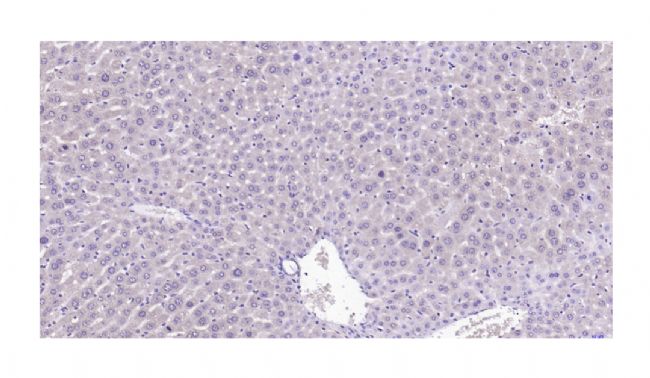

在使用檢測進行診斷之前,必須了解反應在細胞或組織內的預期抗原分布。如下圖所示,CD79a 抗體僅染色了漿細胞瘤細胞的細胞核。根據目前對該抗原位置(細胞質和細胞質膜) 的了解,該反應被認為不是特異性的。

下部插圖是異常染色的細節;上部插圖描繪了漿細胞瘤中 CD79a 的典型細胞質染色。條 = 60 μm,兩個插圖條 = 5 μm。